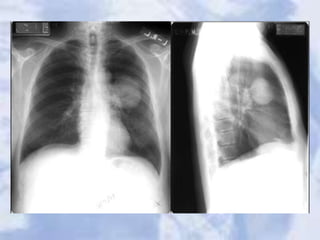

CHF:a great deal of accentuated interstitial markings,

Curly lines, and an enlarged heart. Normally indistinct

upper lobe vessels are prominent but are also masked

by interstitial edema.

24 hours after diuretic therapy